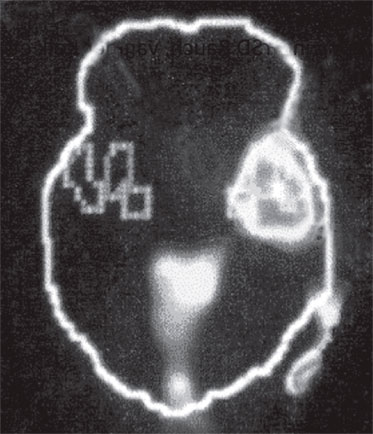

А. Правая лимбическая область

Б. Зрительная кора

В. Зона Брока

Изображение мозга в процессе переживания травмы. Светлые пятна в лимбической коре (А) и зрительной коре (Б) соответствуют повышенной активности мозга в этих участках. На снимке (В) видна значительно пониженная активность речевого центра мозга.

Когда через эту процедуру прошли все восемь участников, Скотт Рауч вместе со своими математиками и статистиками взялся за создание составного снимка, по которому можно было бы наглядно сравнить активность мозга в нейтральном состоянии и в момент появления неприятных воспоминаний. Несколько недель спустя он отправил мне результаты, которые вы видите выше. Я приклеил эти снимки на дверцу своего холодильника в кухне и на протяжении следующих нескольких месяцев каждый вечер их разглядывал. Должно быть, именно так чувствовали себя первые астрономы, взглянув через телескоп на неизученное звездное скопление.

На снимках были некоторые сбивающие с толку точки и цвета, однако самая яркая область активации мозга – большое красное пятно в правом нижнем центре мозга, известном как лимбическая область, или эмоциональный мозг, – никакого удивления не вызывала. Мы уже знали, что сильные эмоции активируют лимбическую систему, в особенности участок внутри нее, известный как миндалевидное тело.

Миндалевидное тело предупреждает нас о надвигающейся опасности, активируя стрессовую реакцию организма. Наше исследование явно показало, что у переживших травму людей определенные образы, звуки или мысли, связанные с их конкретными переживаниями, миндалевидное тело начинает бить тревогу – даже, как это было в случае с Маршей, спустя тринадцать лет после самого происшествия.